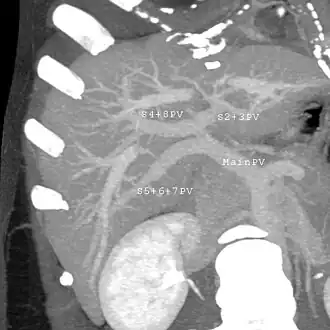

With the recent advances of noninvasive imaging, living liver donors usually have to undergo imaging examinations for liver anatomy to decide if the anatomy is feasible for donation. The evaluation is usually performed by multidetector row computed tomography (MDCT) and magnetic resonance imaging (MRI). MDCT is good in vascular anatomy and volumetry. MRI is used for biliary tree anatomy. Donors with very unusual vascular anatomy, which makes them unsuitable for donation, could be screened out to avoid unnecessary operations.

MDCT image. 3D image created by MDCT can clearly visualize the liver, measure the liver volume, and plan the dissection plane to facilitate the liver transplantation procedure. -